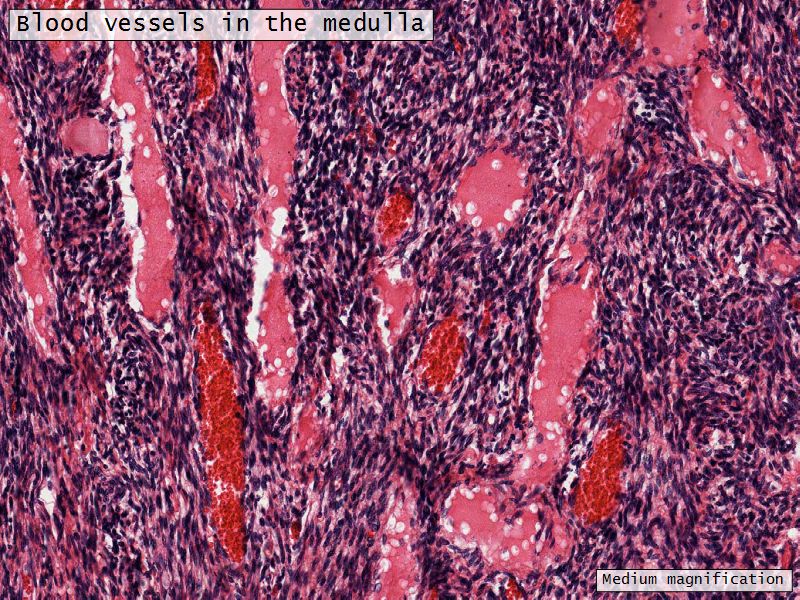

Medulla

- Blood vessels

- Hilus cells

- Stroma

Blood vessels

- Enter medulla at hilus

- Supply the cortex

- Epithelioid cells clump around blood vessels

Epithelioid cells

- Located in hilus

- Also called hilus cells

- Clump around blood vessels

- ≈ Leydig cells

- Probably produces androgens